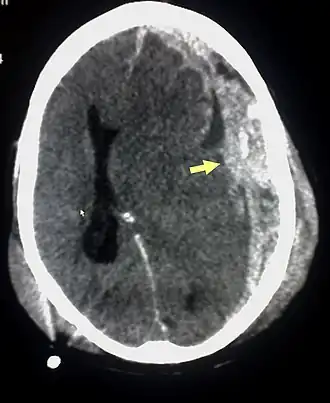

![]() TAC mostrando contusiones cerebrales, hemorragia intracraneal entre los hemisferios, hematoma subdural y fracturas craneales[1] | ||